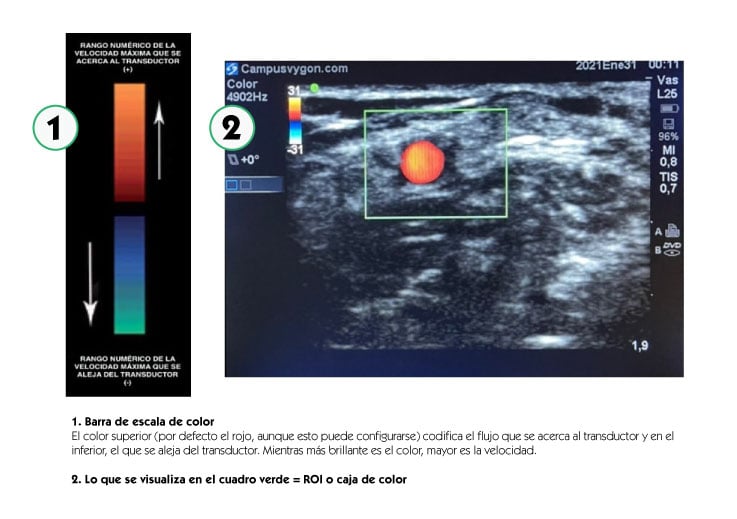

Mediante la aplicación del modo doppler color, se codifica la velocidad media del flujo estudiado, asignándole un color que va a estar determinado en relación con el sentido del flujo, de acuerdo con una determinada escala, superponiéndola a la imagen en Modo B (bidimensional o escala en blanco y negro). El ROI (Region Of Interest: Zona De Interés) o caja de color, determinará la zona de muestreo.

Manteniendo la exploración en modo B, activamos el modo doppler color y situamos el ROI o cuadro de color en la estructura que queramos estudiar, asignando un tamaño adecuado al mismo.

Posteriormente, angulamos el transductor entre 30 a 60º o bien hacia la parte distal del cuerpo (hacia la mano), o hacia la parte proximal (hacia la cabeza). Por último, volvemos a activar el modo doppler color para que comience el análisis, obteniendo una tonalidad roja al identificar el flujo que fluye hacia el transductor o azul si éste, se aleja.